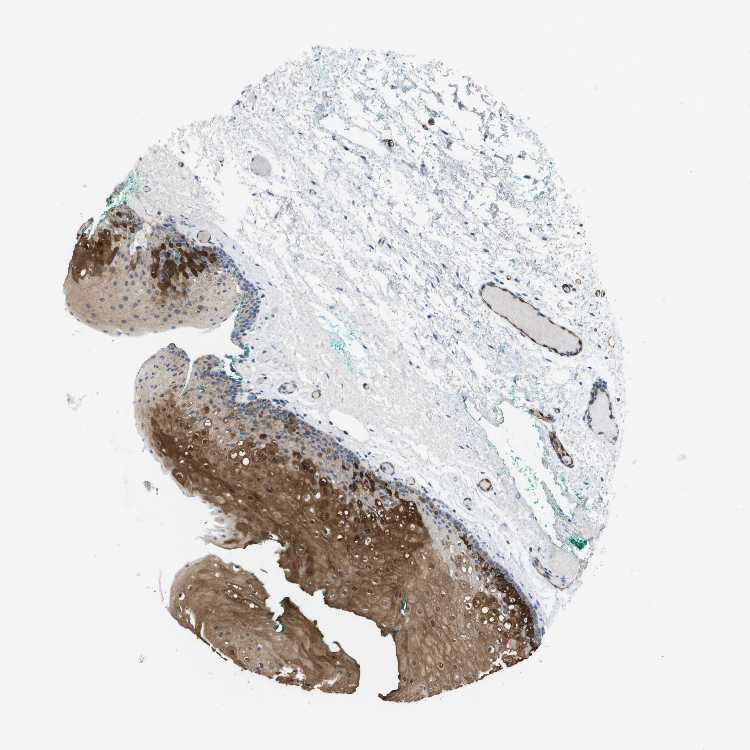

TISSUE PRIMARY DATA ORAL MUCOSA Show tissue menu

Oral mucosa

ORAL MUCOSA - Antibody stainingi

Antibody staining in the annotated cell types in the current human tissue is reported as not detected, low, medium, or high, based on conventional immunohistochemistry profiling in selected tissues. This score is based on the combination of the staining intensity and fraction of stained cells.

Each image is clickable and will lead to virtual microscopy that enables deeper exploration of all samples and also displays staining intensity scores, fraction scores and subcellular localization as well as patient and tissue information for each sample.

Antibody HPA051895Antibody CAB017831Antibody CAB040577

Squamous epithelial cells HighHighHigh